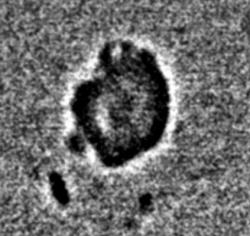

Протокол исследования. Общий фон инволютивно измененной молочной железы (в годы климакса). В правой молочной железе в передних отделах, в верхнем наружном квадранте определяется «узловое образование» значительной интенсивности, однородной структуры (1), неправильно округлой формы, с неровными, местами волнистыми контурами. В окружающей ткани определяются несколько различных размеров очаговых теней значительной плотности. Описанные тени располагаются на фоне локального снижения прозрачности молочной железы (стрелки) – по всей видимости - участок нежного склероза (1 – прямая проекция, 2 – боковая проекция). 3, 4, 5 – патологический участок железы выделен «навигатором», проведена цифровая обработка изображения – тень неоднородной структуры с преимущественным обызвествлением по периферии и известковыми включениями в центре.

Заключение: Инволютивная молочная железы в годы климакса. Фиброаденома (обызвествленная) правой молочной железы с более мелкими обызвествленными фиброаденомами вокруг.